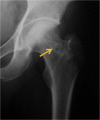

Steroid-associated osteonecrosis (SAON) is a common orthopaedic problem caused by administration of corticosteroids prescribed for many nonorthopaedic medical conditions. We summarised different pathophysiologies of SAON which have adverse effects on multiple systems such as bone marrow stem cells (BMSCs) pool, bone matrix, cell apoptosis, lipid metabolism, and angiogenesis. Different animal models were introduced to mimic the pathophysiology of SAON and for testing the efficacy of both prevention and treatment effects of various chemical drugs, biological, and physical therapies. According to the classification of SAON, several prevention and treatment methods are applied at the different stages of SAON. For the current period, Chinese herbs may also have the potential to prevent the occurrence of SAON. In the future, genetic analysis might also be helpful to effectively predict the development of ON and provide information for personalised prevention and treatment of patients with SAON.